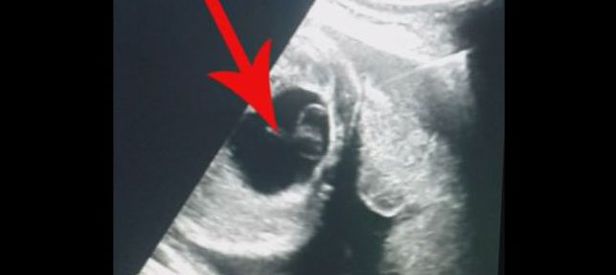

Çapar, hamileliğin 30. haftasında anne karnındaki bebek için ameliyat kararı aldı. Gerçekleştirilen cerrahi operasyonla bebekteki 6 santimetre civarındaki yumurtalık kisti başarılı şekilde alındı.

Sorunlu doğma ihtimalinin önüne geçildi

Bu nedenle anne karnındaki çocuğun kistini operasyonla aldıklarına dikkati çeken Çapar, "Kontrollerde kistin kalmadığını gördük. Anne karnında ameliyat yapılarak doğum sonrasında gelişebilecek birçok problemin önüne geçtik" diye konuştu.